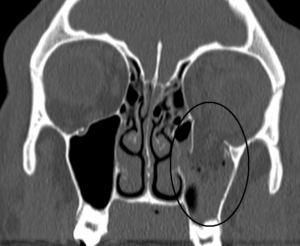

Pblowoutfracture

DIAGNOSING ORBITAL BLOW-OUT FRACTURES

Warning signs of orbital blow-out fracture include bruising around the eye, double vision, protrusion of the eye, and/or numbness in the cheek and upper teeth areas. The ocular plastic surgeon will examine the eye carefully whether it has been damaged. A CT scan will also be performed to assess the extent of the fracture.

Emergency Trauma services in Mumbai are available at Wavikar Eye Hospital. Based on the complete evaluation, your ocular plastic surgeon may recommend surgery. Factors influencing the timing of surgery include persistence of double vision, enophthalmos (the eye appears shrunken in the orbit as the swelling subsides), any limitation of eye movements, and the size of the fracture.